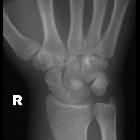

- lateral radiograph

- lunate seen displaced and angulated volarly

- 'spilled teacup' appearance

- lunate does not articulate with capitate or radius (as opposed to perilunate dislocation where the lunate remains aligned with the radius)